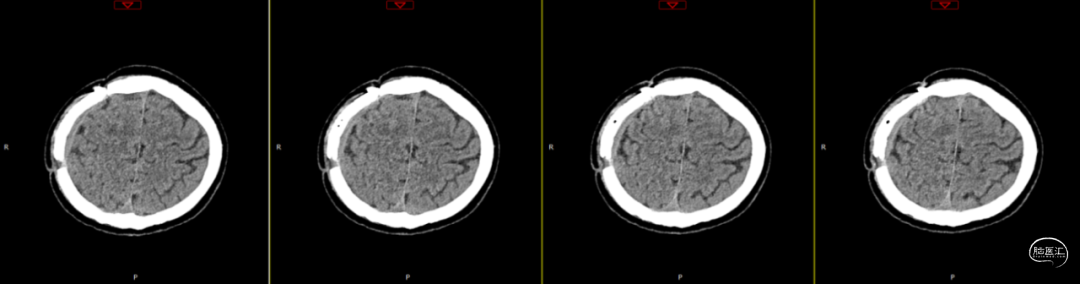

2024-07-21 08:58:55术后58天复查(如上图)。

术后58天颅脑磁共振平扫(如上图):右侧额顶颞部见斑片状异常信号,呈片状T1WI低、T2WI稍高信号影,T2FLAIR呈稍高信号,边界清,右侧额顶颞叶脑组织受压,DWI(b=1000)呈混杂高信号,相应ADC呈混杂高信号影。